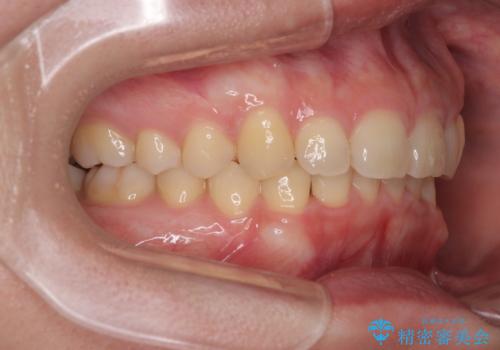

下顎臼歯を起き上がらせるためにユーティリティーアーチを使用し、一気に深い咬み合わせを改善することができました。